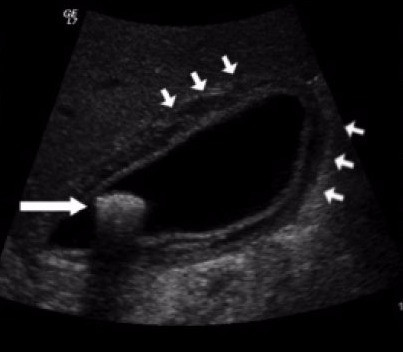

Qual o diagnóstico?

Abdome agudo hemorrágico